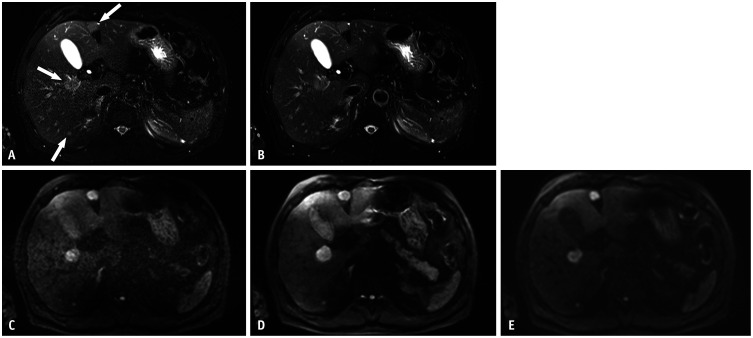

Objective: To compare a deep learning (DL)-accelerated non-enhanced abbreviated MRI (AMRIDL) protocol with standard AMRI (AMRISTD) of the liver in terms of image quality and malignant focal lesion detection.

Materials and methods: This retrospective study included 155 consecutive patients (110 male; mean age 62.4 ± 11 years) from two sites who underwent standard liver MRI and additional AMRIDL sequences, specifically DL-accelerated single-shot fast-spin echo (SSFSEDL) and DL-accelerated diffusion-weighted imaging (DWIDL). Additional MRI phantom experiments assessed signal-to-noise ratio (SNR), contrast-to-noise ratio (CNR), and apparent diffusion coefficient (ADC) values. Three reviewers evaluated AMRIDL and AMRISTD protocols for image quality using a five-point Likert scale and identified malignant hepatic lesions. Image quality scores and per-lesion sensitivities were compared between AMRIDL and AMRISTD using the Wilcoxon signed-rank test and logistic regression with generalized estimating equations, respectively.

Results: Phantom experiments demonstrated comparable SNR and higher CNR for SSFSEDL compared to SSFSESTD, with similar ADC values for DWIDL and DWISTD. Among the 155 patients, 130 (83.9%) had chronic liver disease or a history of intra- or extrahepatic malignancy. Of 104 malignant focal lesions in 64 patients, 58 (55.8%) were hepatocellular carcinomas (HCCs), 38 (36.5%) were metastases, four (3.8%) were cholangiocarcinomas, and four (3.8%) were lymphomas. The pooled per-lesion sensitivity across three readers was 97.6% for AMRIDL, comparable to 97.6% for AMRISTD. Compared with AMRISTD, AMRIDL demonstrated superior image quality regarding structural sharpness, artifacts, and noise (all P < 0.001) and reduced the average scan time by approximately 50% (2 min 29 sec vs. 4 min 11 sec). In patients with chronic liver disease, AMRIDL achieved a 96.6% per-lesion sensitivity for HCC detection, similar to 96.5% for AMRISTD (P > 0.05).

Conclusion: The AMRIDL protocol offers comparable sensitivity for detecting malignant focal lesions, including HCC while significantly enhancing image quality and reducing scan time by approximately 50% compared to AMRISTD.